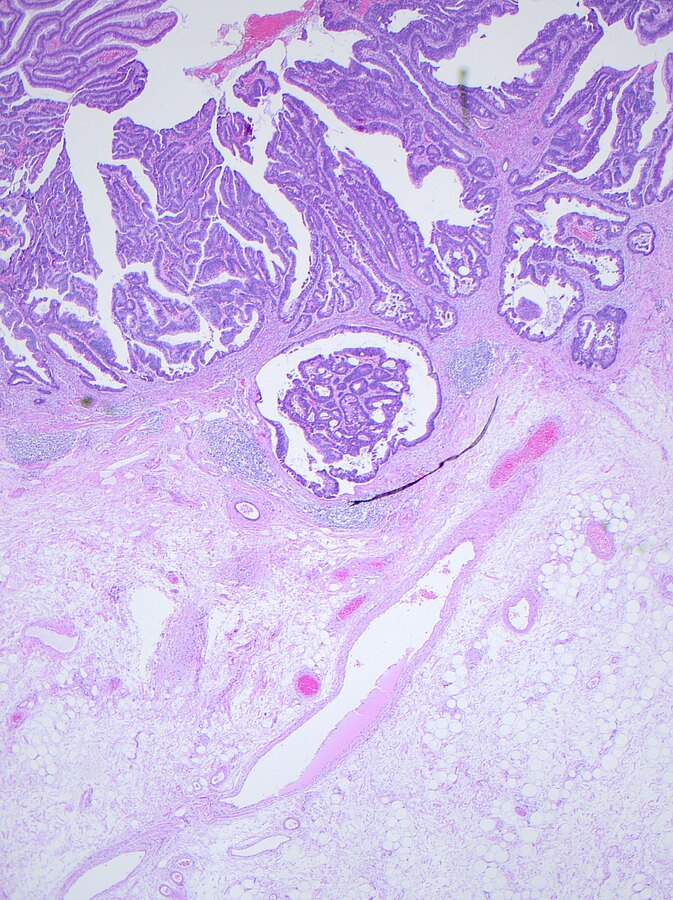

Je früher, desto besser. „Wenn wir den Darmkrebs in seinem ersten Stadium erkennen, können wir statistisch gesehen neun von zehn Patienten heilen“, sagt Privatdozent Dr. Steffen Mühldorfer, Chefarzt der Klinik für Gastroenterologie und Leiter des Darmzentrums. Doch noch immer ist Darmkrebs die zweithäufigste Krebstodesursache in Deutschland. Nach Angaben des Robert-Koch-Instituts sterben daran jährlich mehr als 25.000 Menschen. Mühldorfer rät deshalb zur Vorsorge. Jährlich sollten Patienten ab 50 ihren Stuhl auf Blutspuren untersuchen lassen. In absehbarer Zukunft wird sich das Analyseverfahren verbessern. Ein immunologischer Test soll zuverlässigere Ergebnisse liefern. Doch der Chefarzt sagt auch: Selbst der beste Test kommt nur etwa 60 Prozent der Darmkrebsfälle auf die Spur. „Mit Hilfe von Vorsorgekoloskopien, also von Darmspiegelungen, wäre ein Durchbruch möglich. Denn damit lässt sich die Krebsrate um bis zu 90 Prozent senken.“ Bei einer Darmspiegelung erkennen und entfernen Mediziner Polypen – sie sind die Vorstufe eines Karzinoms. Bereits seit 2002 übernehmen Krankenkassen für Patienten ab dem vollendeten 55. Lebensjahr die Kosten für eine Darmspiegelung. Doch in den Jahren zwischen 2002 und 2012 haben pro Jahr nur 400.000 von insgesamt 16,7 Millionen Versicherten, die einen Anspruch auf eine Darmspiegelung hatten, tatsächlich davon Gebrauch gemacht. Der Anteil bei den Frauen liegt bei 22, bei den Männern bei 20 Prozent. „Ich rate jedem Anspruchsberechtigtem zu einer Darmspiegelung. Und wenn die abgelehnt wird zumindest zu einem Stuhltest “, sagt Mühldorfer. Denn je früher Darmkrebs erkannt wird, desto besser die Heilungschancen.

Privatdozent Dr. Steffen Mühldorfer rät zur Darmspiegelung als wirksamste Vorsorgemethode gegen Darmkrebs.